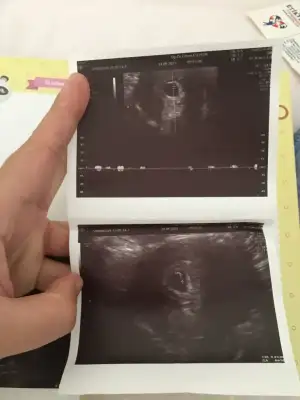

Cinsiyet tahmini

Bana da yorum yaparmışsınız 11+4.

Bana da bakar misinizKiz Bebeknub gözüküyor sanki

Merhaba bana da yorum yapabılır mısınız rıca etsem 2.foto 6+1 günlük karındanRamzi teorisi var.ona gore soyledim ama ne kdr gercekci bilemiyorumsonucta kanitlanmis birsey degil bence